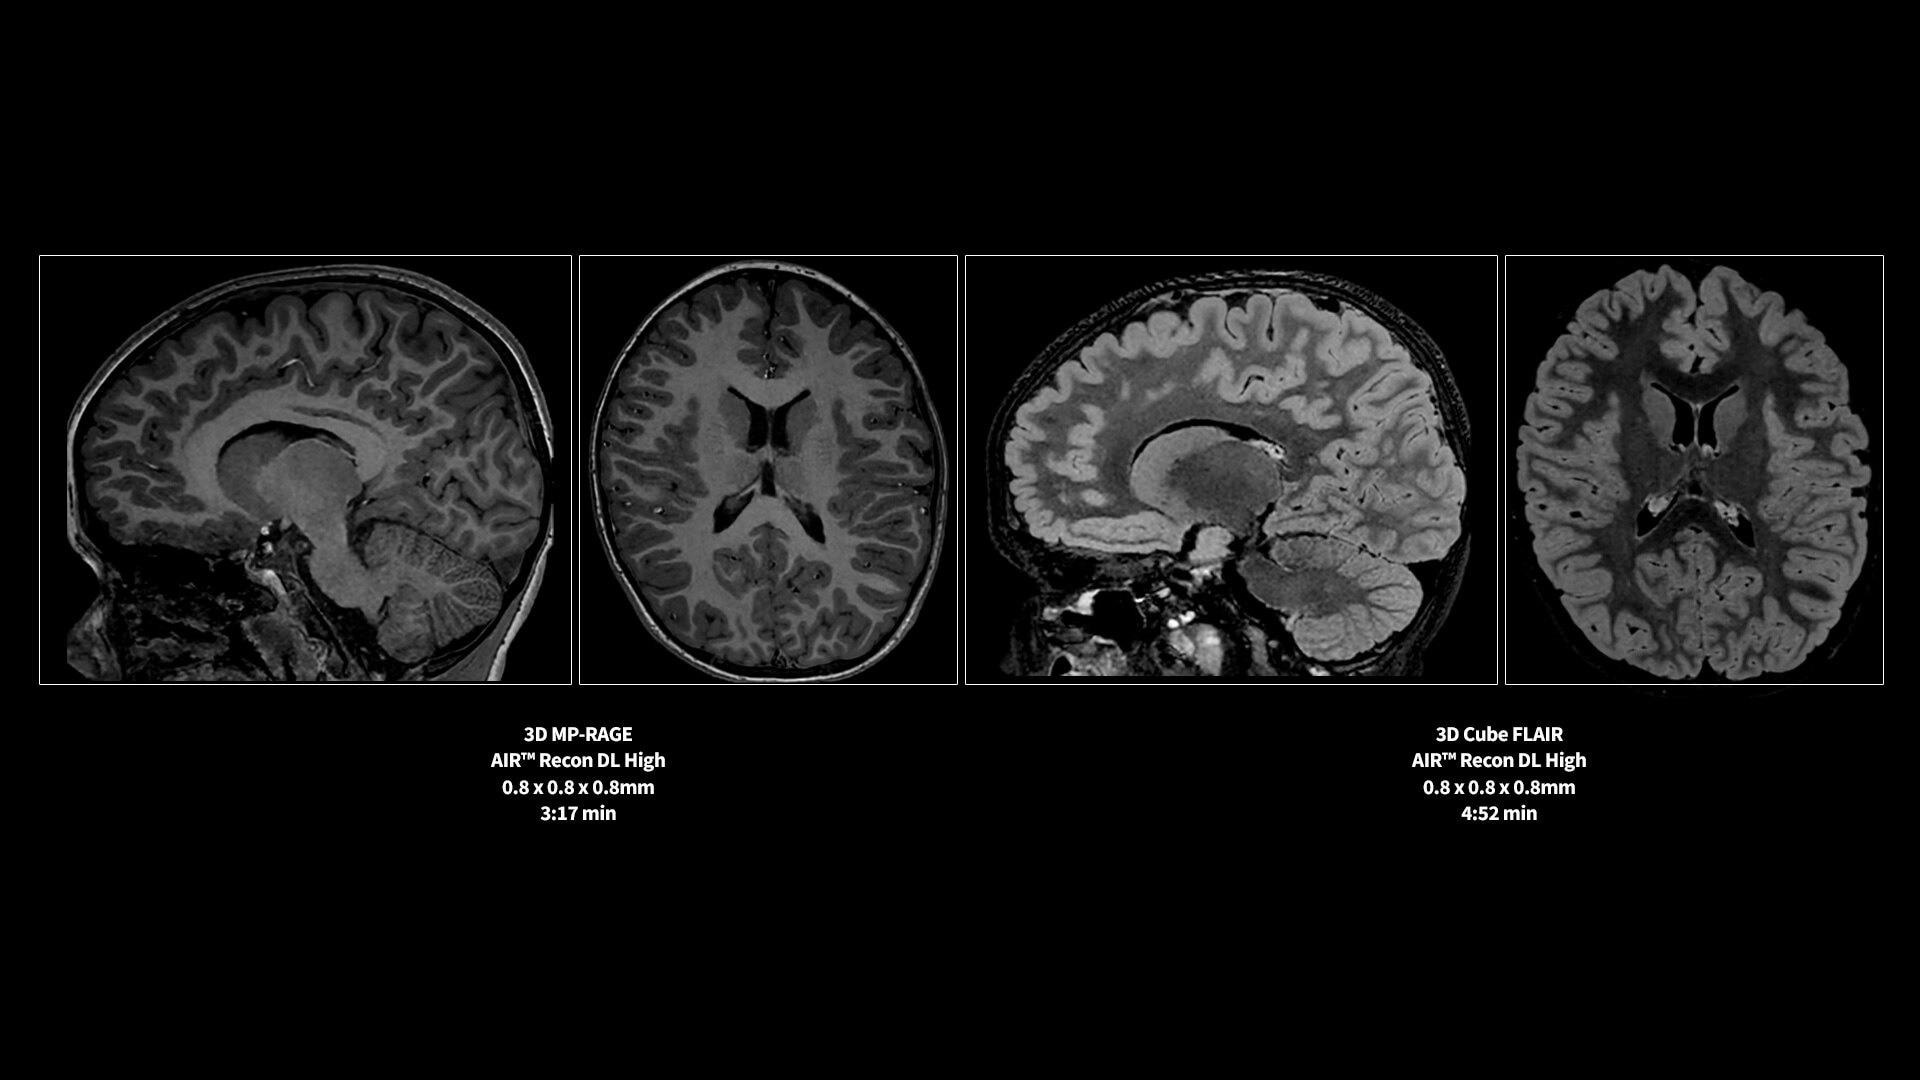

<p>AIR Recon DL</p>

Learn more ico-caret-right

MR image reconstruction with AIR Recon DL

Evolve your MRI scanner's capabilities: experience exceptional image quality without compromising scan time.